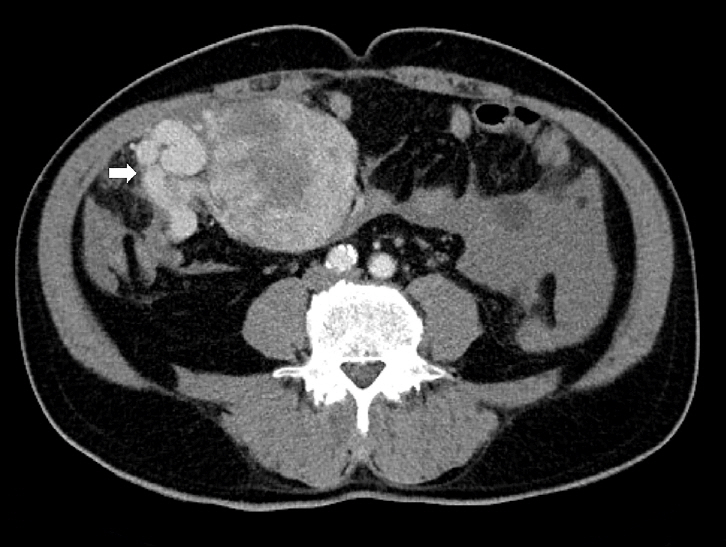

Upon imaging, SFTs typically show nonspecific radiographic features [60,61], whereas computed tomography (CT) usually yields a well-defined, occasionally lobulated, isodense mass relative to the skeletal muscle (Fig. 1). They exhibit heterogeneous contrast enhancement because of their rich vascularity [62,63]. Magnetic resonance imaging (MRI) typically shows intermediate T1 signal intensity and variable T2 signals, which correspond to fibrous (low T2) and cellular or myxoid (high T2) components [63-65]. Larger or more aggressive tumors may display heterogeneity because of fibrosis, necrosis, hemorrhage, or cystic changes [63].

Fig. 1.

Radiological findings of solitary fibrous tumor. Axial contrast-enhanced abdominal computed tomography demonstrates a large central abdominal mass. Prominent feeding vessels (arrow) are visible along the anterior aspect of the lesion.